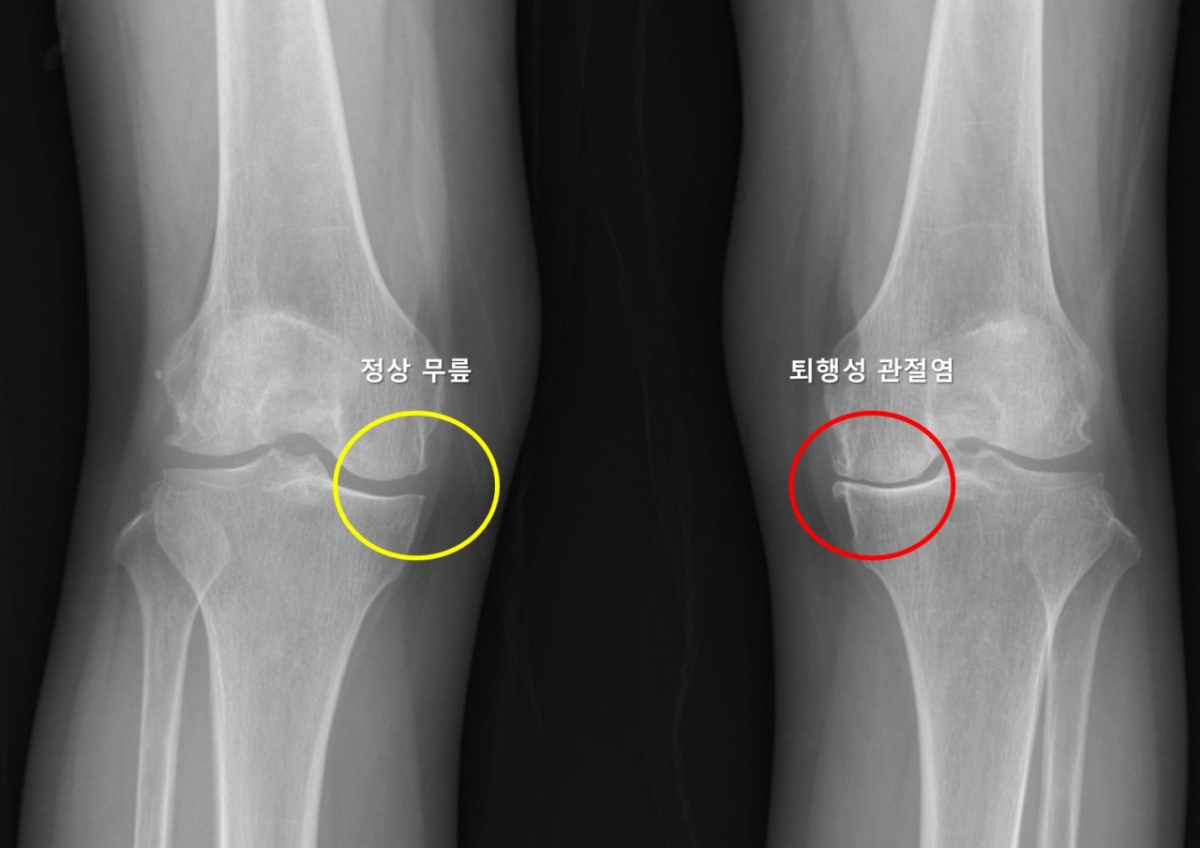

한쪽 무릎에 퇴행성 관절염이 생긴 환자는 다른쪽 무릎에도 똑같은 병이 생기지 않을지 불안에 떨어야 했다. 많은 환자가 한쪽 무릎에 관절염이 생긴 뒤 수년 내 반대쪽 무릎에서도 통증, 구조적 변화가 나타나는 경험을 한다. 하지만 이러한 양측성 진행이 모든 환자에게서 똑같이 나타나지 않아, 이를 예측하려는 연구는 부족했다. 그런데 서울대병원 연구팀이 이런 예측을 가능하게 하는 머신러닝 기반 모델을 개발하는 데 성공했다.

또 기존 관절염이 있는 무릎의 관절염 정도(KLG)와 통증 및 기능 지표(WOMAC 점수)가 반대쪽 무릎 퇴행성 관절염 발생과 유의미한 연관성을 보인 것은 이번 연구에서 처음 확인된 중요한 결과다. 성별이나 BMI 등 기존에 알려진 일반적 위험 요인 외에도, 반대쪽 무릎 자체의 구조적 특성이 관절염 발생 예측에 중요한 역할을 했으며, 이전까지 잘 알려지지 않았던 외측 관절 간격 감소가 핵심 예측 요인으로 확인된 점 역시 이번 연구의 의미 있는 발견으로 꼽힌다.